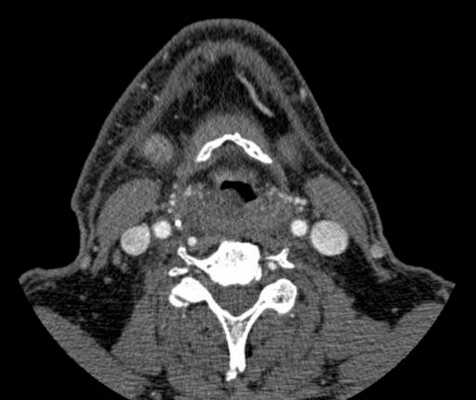

Объемное образование в области гортани (стрелки): проекция спереди и сбоку

МРТ показывает рак гортани и других органов. Томография является предпочтительным методом визуализации новообразований. Чтобы улучшить достоверность и качество снимков, врачи рекомендуют проводить исследование с контрастированием. МРТ покажет:

- размер очага;

- расположение опухоли;

- контур и внутреннюю структуру;

- особенности кровотока;

- состояние лимфатических узлов и др.

При помощи полученных данных доктор сможет установить диагноз, предположить, есть ли у новообразования злокачественный потенциал, определить наличие метастазов и стадию заболевания. Раковая опухоль чаще выглядит как бугристый элемент, прорастает соседние ткани. Биопсия (метод диагностики, дающий информацию о клеточном строении), имеет решающее значение в подтверждении онкологии. Результаты томографии помогут определить тактику лечения, объем операции, сделать прогноз при раке горла, покажут динамику состояния.